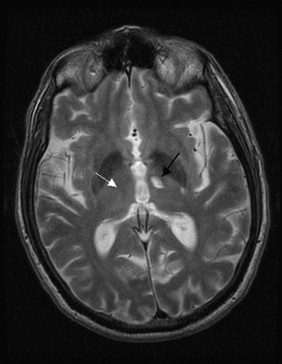

Stroke Syndrome:

“Dejerine and Roussy” Syndrome - Thalamic (on this case on the right). Infarction of sensory relay nucli due to occlusion of thalamogeniculates. These come from the PCA